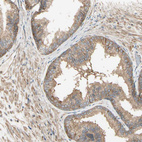

Immunohistochemical staining of human prostate shows moderate perinuclear and cytoplasmic positivity in glandular cells.